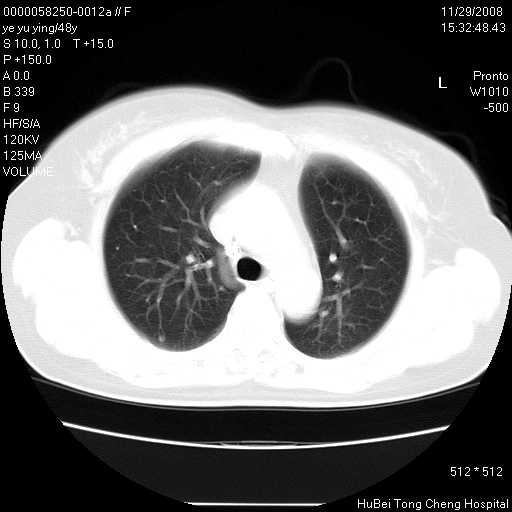

以下是引用zsl6918在2008-11-29 21:47:00的发言:[br]恶性肿瘤病史,转移瘤首先考虑。脂肪肝,胆囊结石。

以下是引用huenhao在2008-11-29 22:11:00的发言:[br]脂肪肝,胆囊结石。左肺病灶建议定期复查。

以下是引用liuyue在2008-11-30 5:44:00的发言:[br]1.左肺病变,首先考虑感染性病变,转移待排;建议治疗后复查。[br]2.肝脏密度普遍减低,考虑与化疗有关。[br]3.胆囊结石.